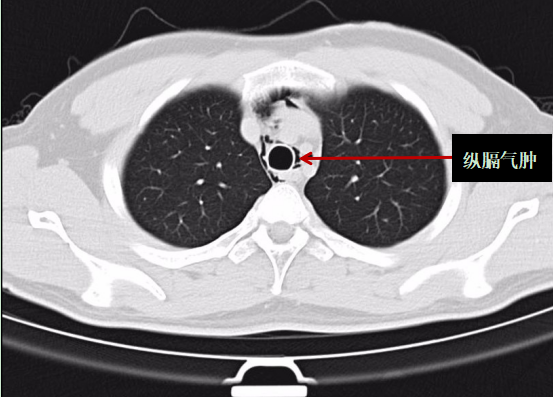

医生表示:根据胸部CT报告,阿岳被诊断为"自发性纵膈气肿",即颈部软组织、纵隔气肿。所幸送医及时,不然后果不堪设想。

阿岳的胸部CT影像